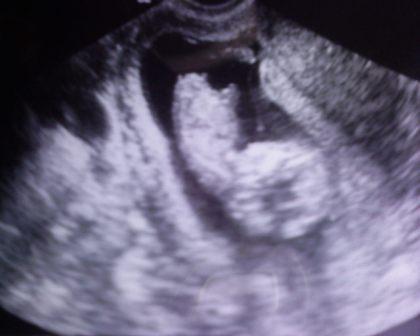

Eddig még csak a másik topikba irtam ide még

babonábol nem mertem ,de azt hiszem mostmár itt az ideje

hogy csatlakozzak hozzátok ma vagyunk 12+1 naposak

és ma voltunk ultrahangon 6 cm a baba és láttam ahogy mozog.

Nagyon édes volt!Nyaki redöt is mértek 1,6mm.